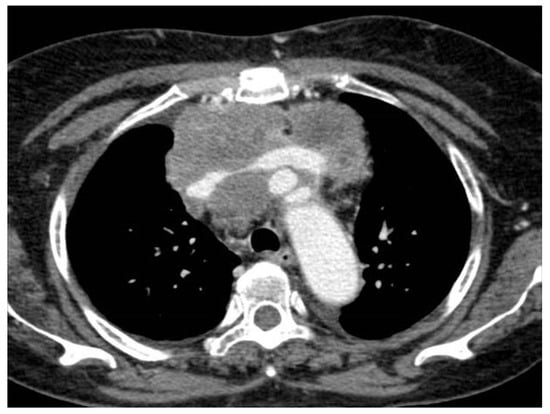

3. Unusual Radiological Presentation

- Hassan, I.; Goolam-Mahomed, A. An unusual cause of an anterior mediastinal mass. Respir. Med. Case Rep. 2014, 12, 52–54. [Google Scholar] [CrossRef]

- Knipscheer, B.; Kromontono, R.; De Bruin, P.; Van Strijen, M.; Herder, G. Two malignancies or an unusual presentation of a pleural malignancy? Lung Cancer 2013, 81, 306–307. [Google Scholar] [CrossRef] [PubMed]